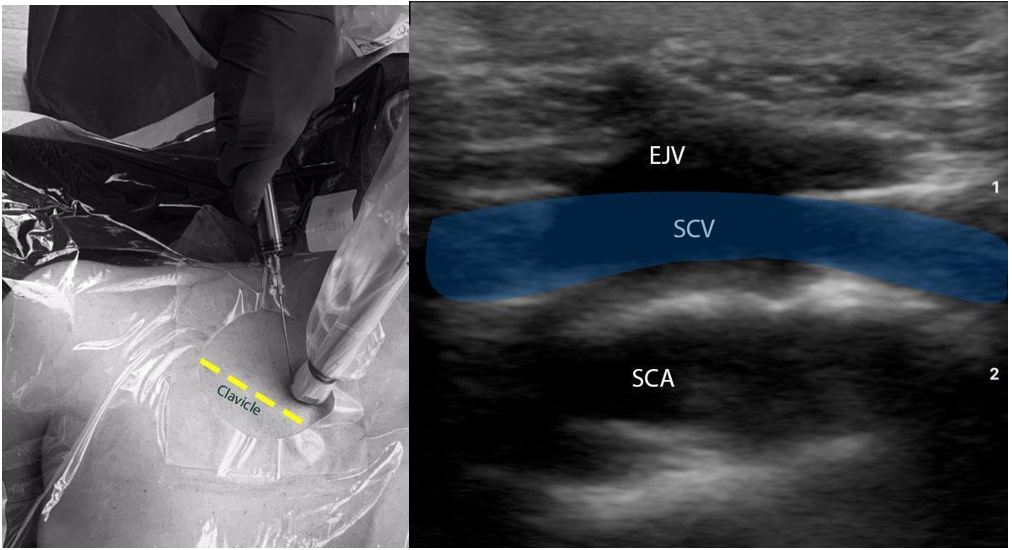

New CardioCrit video! There might be another way to do pericardiocentesis — and it’s worth seeing. @KartikThinks @msenussiMD